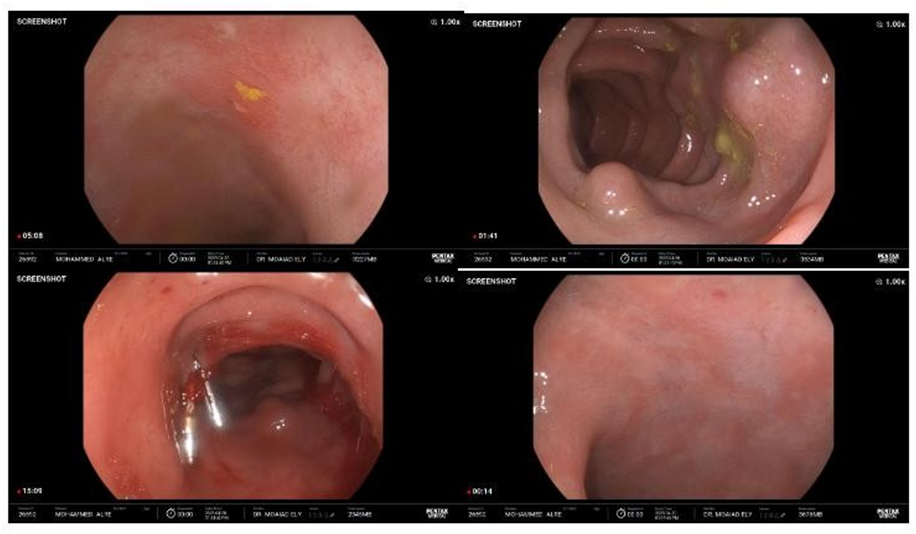

· Colonoscopy:

- Ulceration and inflammation noted in the terminal ileum

- Inflamed rectal mucosa

- A small polyp in the left colon; biopsy resulted in active spurting hemorrhage, suggesting underlying varices

The Varices at left side and descending colon, Biopsied small polyp – active spurting bleeding >> small varices